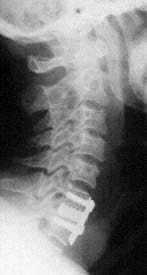

In both types of implants (glassceramics/bioactive titanium) developed by us we indicated patients for the operation according to the instability of the injured lower spine defined in the preoperational stage according to the imaging methods (X-ray, MRI, CT) and using the classification according to Aebi and Nazarian and according to the neurological findings using the Frankel scale. We carried out the surgery by the Caspar technique (Caspar 1989, Klézl 1999). Under general anesthesia from the prevertebral incision and after exposing anterior surface of the veretbral bodies we removed the structures compressing the spinal canal (intervertebral disk, posterior ligament residues, fragments of the edges of the vertebral bodies, haematoma, etc.) using an operating microscope. Then we prepared a bed for inserting the implant into the interbody space. We removed the endplates from the vertebral bodies and exposed cancellous bone. In traction and using the Caspar´s instrumentarium we inserted the implant into the interbody space under the control of X-ray, see Figure 7.

Figure 7 : Inserting the bio-titanium implant into the interbody space C5/6 using the X-ray control After releasing traction and checking the position on X-ray we fixed the impaired segment by a plate secured with monocortical or bicortical screws into the neighboring vertebral bodies. Surgical procedure is similar for both the glass-ceramics implant and the biotitanium implant. We used the same surgical procedure for other types of implants as well (polyactide/PEEK). We carried out verticalization in operated patients in case of all implants on the first post-operative day in a collar for a period of 6 weeks until the expected bone fusion occurrence.

At Neurosurgery Department of the University Hospital in Ostrava we operated 10 patients with unstable injury to the lower cervical spine using glassceramics implants between 1997 and 1999, see Figures 9 and 10 The implant for use in ACIF made of glassceramics fulfilled our expectations. It removed complications associated with bone graft harvest and due to its shape and bioactive properties it enabled a chemical bond with surrounding osseous tissue to create bone fusion without a need for filling with other material (Bienik 1991,Madawi 1996, Filip 2000). Its disadvantages included fragility in contact with metal and threshold bending strength. These disadvantages were eliminated by a new implant made of bio-titanium that we introduced into clinical practice for identical indications in 2004. In years 2007-2011 at the Neurosurgery Department of KNTB Zlín we operated 34 patients with unstable lower cervical spine injury. In 12 patients we used a bio-titanium implant in ACIF (Figures 11 and 12). In 22 patients we used an implant made of different materials (Figure 13). In our own set of patients we evaluated the neurological finding according to the Frankel scale with a finding from the imaging methods (X-ray, CT, MRI) preoperative and 2, 6 and 12 months after the surgery.